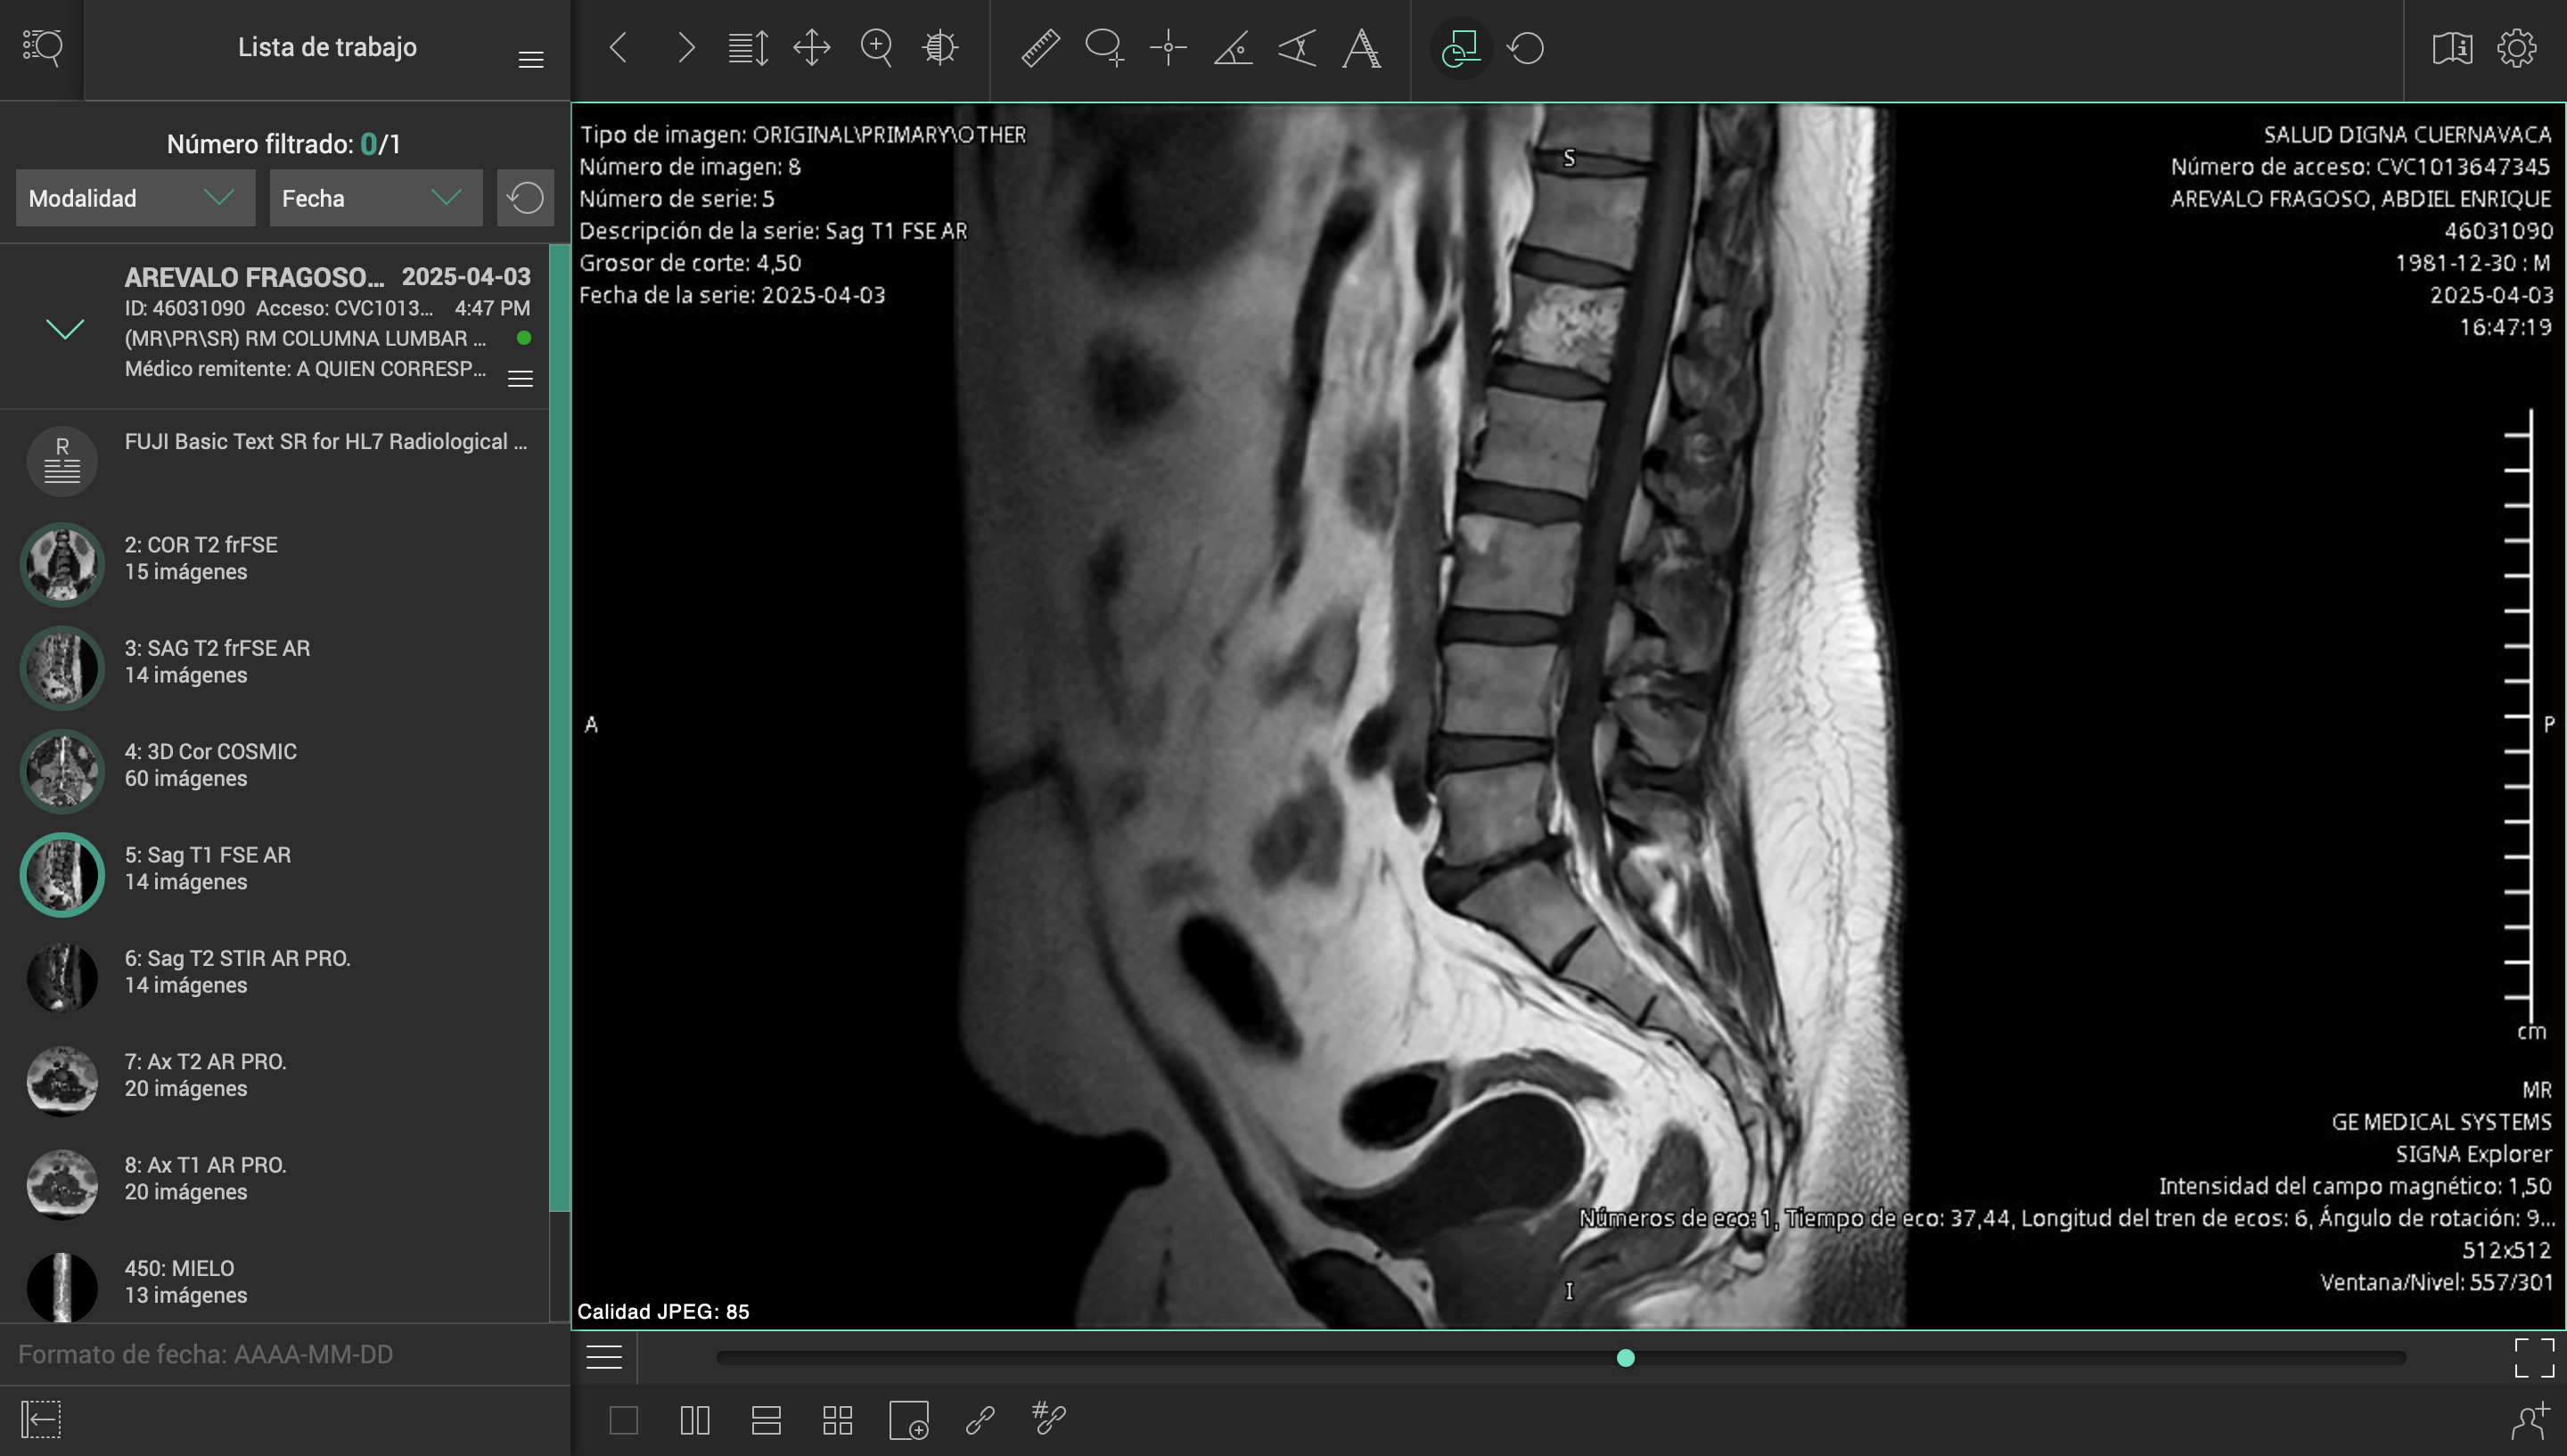

El pasado 2 de marzo de 2025, sufrí un accidente en carretera mientras conducía mi motocicleta. Un automóvil me impactó y me arrojó contra el asfalto, causándome lesiones severas en el hombro izquierdo, columna cervical y lumbar. El conductor se dio a la fuga, y hasta ahora no ha sido posible obtener justicia ni apoyo institucional.

Desde entonces, han pasado más de tres meses esperando una consulta con un especialista del ISSSTE, sin éxito. Durante este tiempo, mi salud ha empeorado, con complicaciones cada vez mayores por la falta de atención médica oportuna.

Esta situación me ha colocado en una condición muy vulnerable, médica, emocional y económicamente. Los tratamientos, terapias y cirugías necesarias superan los casi un millón de pesos mexicanos, una cifra que me resulta imposible cubrir por mi cuenta.